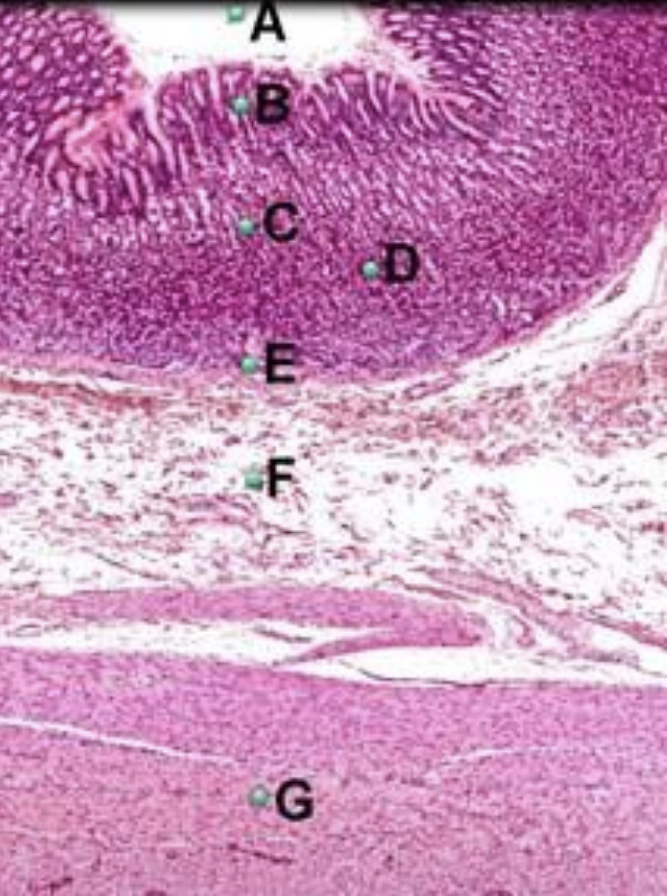

Part A?

lumen of stomach

Part B?

epithelium of stomach

Part C?

mucosa of stomach

Part D?

lamina propria of stomach

Part E?

Muscularis mucosae of stomach

Part F?

submucosa of stomach

Part G?

muscularis externa of stomach